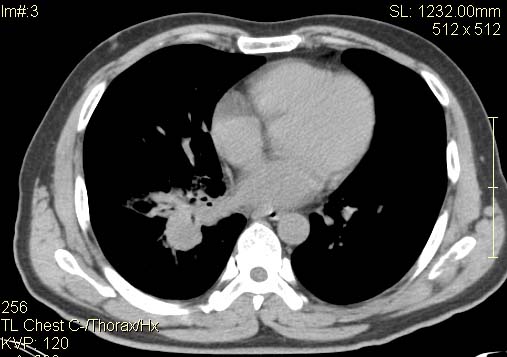

以下是引用qingyuan在2007-4-17 14:19:00的发言:[br]右肺下叶外侧后段胸膜下区节结样病变、分叶、内可见空洞,壁厚薄不均,胸膜凹陷、肺门周围区纹理增粗、僵硬、并近似小结节样改变,肺门区软组织节结、纵膈淋巴结肿大,患者病史长、抗炎治疗无好转炎性改变基本排除,考虑:右肺下叶周围型肺癌伴纵膈及右肺门区淋巴结转移、肺内淋巴管受侵。